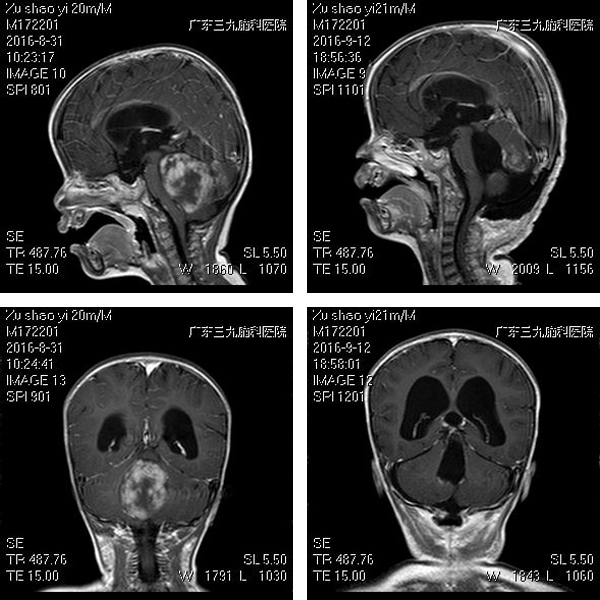

小孩家属10天前突然发现自家小孩1岁8月仍不能独立行走在当地儿童医院就诊,行颅脑磁共振平扫检查发现四脑室内占位病变,并梗阻性脑积水,建议小孩家属进一步完善检查,并手术治疗。患儿家属经协商后决定来广州治疗,近日来广东三九脑科医院神经外七科就诊,门诊行颅脑磁共振检查提示四脑室占位病变,梗阻性脑积水,遂以“四脑室占位病变,梗阻性脑积水”收治入科。入院专科检查:神志清,精神可,可简单对答,双侧瞳孔等大等圆,直径3.0mm,光反应灵敏,眼球运动无异常,视力视野查体不配合,粗测正常,口角无歪斜,颈软,四肢肌力、肌张力未见异常,双侧膝、跟腱反射未见异常,双侧Babinski征阴性,不能独立行走,需搀扶下可勉强行走,可扶固定物体站立,缓慢行走。

血管神经外科吾太华主任在详细了解患儿病情后发现患儿后颅窝内肿瘤病变,四脑室已被肿瘤占满,引起幕上梗阻性脑积水,脑干及小脑受压,目前手术指征明确,需尽快行手术治疗,防治发生高颅压引起的枕骨大孔疝。积极完善术前检查后,于近日在全麻下行右侧侧脑室钻孔外引流术及小脑蚓部,四脑室占位病变切除术,术中见肿瘤呈灰白色,质地较硬,血供一般,对脑干挤压严重,肿瘤较大,给予分块切除,全切肿瘤。术后给予监护治疗,吸氧,抗炎,止血,营养神经,能量支持,预防癫痫等综合治疗。术后病理:水母细胞瘤。术后8天患儿恢复良好,转肿瘤综合中心继续放化疗。

影像学检查结果